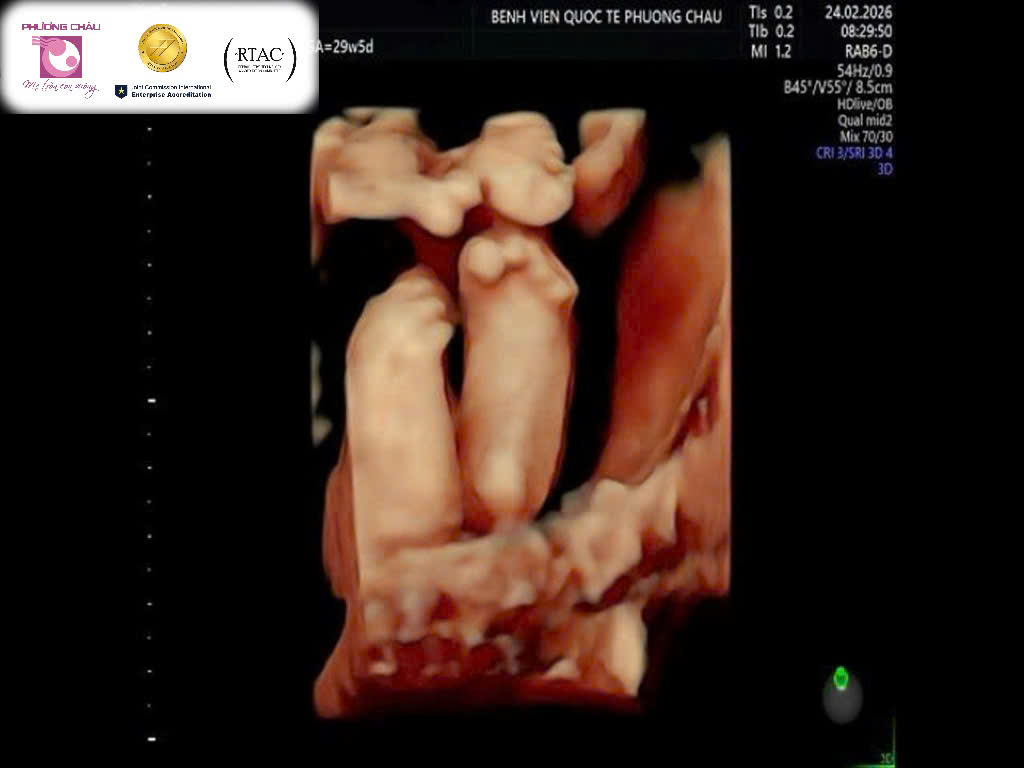

Hội chứng da vảy cá trên siêu âm (nguồn: Bệnh viện Quốc tế Phương Châu)

Từ sự kết hợp của nhiều bất thường đặc trưng, các bác sĩ nghi ngờ thai nhi mắc một hội chứng hiếm gặp: hội chứng da vảy cá (Harlequin Ichthyosis).